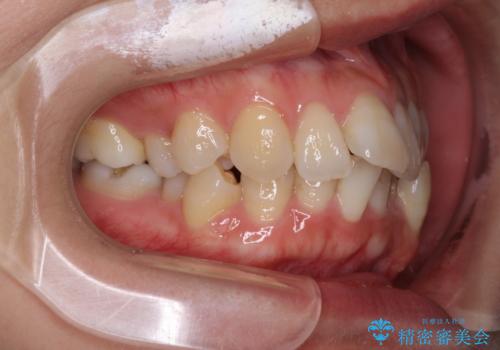

下顎が右左側に変位しているため、左側奥歯の咬み合わせが上下反対の関係となっていました。

また、上下ともに歯列が狭窄しており、奥歯以外にも反対咬合が認められました。

骨格的な問題を抱えた左奥以外は比較的早く咬み合わせが改善しましたが、左奥はどこで咬み合えば良いのか分からず、大変不便な思いをされていました。

ゴムかけにご協力いただき、最終的には反対咬合を改善することができ、患者様には大変満足していただきました。